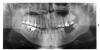

Slovar Опубликовано 5 июля, 2011 Поделиться Опубликовано 5 июля, 2011 Здравствуйте. Прошу о консультации. Мне 29 лет. Всю жизнь были проблемы с зубами, лечил постоянно. Некоторое время назад (около 3 лет) лишился 2 зубов на нижней челюсти слева. К сожалению, так складывалась ситуация, что до этого времени не мог позволить себе полноценное лечение, протезирование или имплантацию. На данный момент созрел, сходил к врачам (имплантологу и ортопеду). В результате один меня убеждает в постановке имплантов и что противопоказаний нет. Другой сказал, что кость истончена, есть риски и лучше ставить мост. Прошу Вас, выскажите по снимку, видите ли Вы какие либо противопоказания к имплантации? Спасибо. Ссылка на комментарий

Bier Опубликовано 6 июля, 2011 Поделиться Опубликовано 6 июля, 2011 по высоте объем костной ткани достаточный, ширину на этом снимке мы не видим. Но если ее не хватает, значит надо сделать предварительное наращивание кости, затем имплантацию. Мост на 8й зуб не очень надежное решение. З.Ы. на других зубах есть проблемы (плохо пролеченные каналы, гранулемы) Ссылка на комментарий